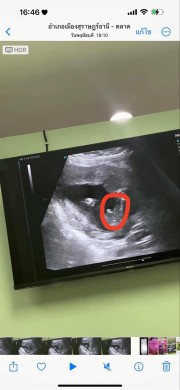

ได้ผู้ชายตามต้องการ ท้องแรก 17 w เห็นอิจู๋แล้วจ้า🥰

ทางนี้ก็โด่มาเหมือนกันเลยค่ะ แม่ดีใจและตื่นเต้นมาก ท้องแรกอยากได้ผช.มากๆ สมใจแล้ว